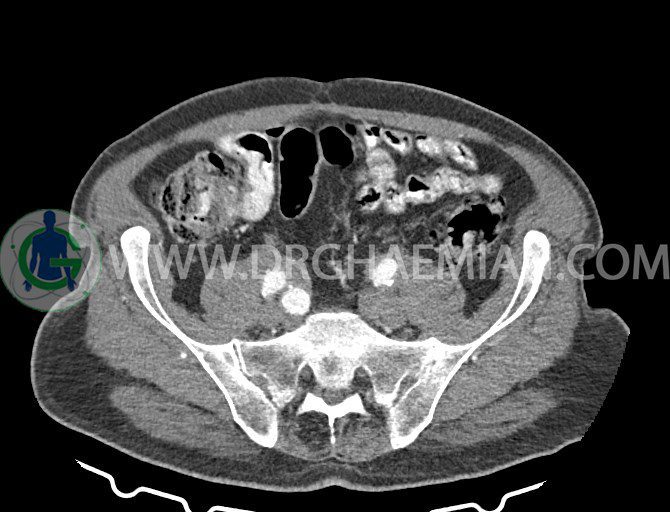

سی تی اسکن لگن یکی از روش های تصویربرداری با سی تی اسکن است. این روش با استفاده از تشعشعات تصاویر عرضی از ناحیه شکمی ایجاد میکند. در این کیس ديورتيكولوزيس، کیست های کورتیکال در هر دو کلیه، لنفادنوپاتی، کلسیفیکاسیون دیواره آئورت و شریان ایلیاک، تغییرات DJD ناحیه توراکولومبار و پروستات بزرگتر از عادی دیده می شود.

در سي تي اسکن اسپيرال شکم و لگن با و بدون کنتراست خوراکی و وريدی (مولتي ديدکتور 16 با مقاطع ظريف و بازسازي هاي ساژيتال و کرونال):

– کيست هاي کورتيکال ساده به قطر 5 mm تا 50 mm در کليه راست و به قطر 5mm تا 55 mm در کليه چپ

– کلسيفيکاسيون ديواره آئورت و شريان ها ايلياک همراه با نشانه هاي ترومبوز مورال در بيفورکاسيون ائورت با امتداد به پروگزيمال هاي شريان هاي ايلياک

لنفادنوپاتي به ابعاد mm 22 x 25 مجاور شريان ايلياک خارجي چپ و به ابعاد mm 17 x 28 مجاور شريان ايلياک خارجي راست

– پروستات به ابعاد mm 45 x 54، بزرگ تر از نرمال

مشهود است.